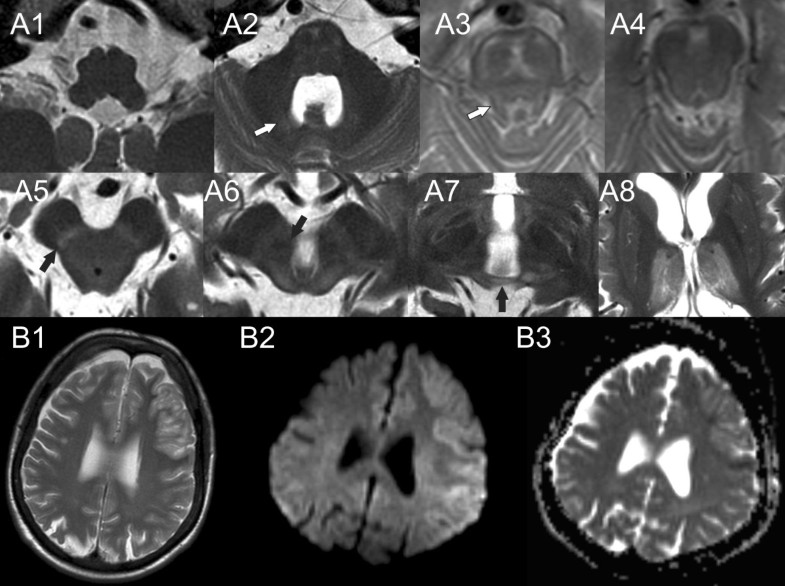

Brain MRI findings in an infant with congenital biotinidase deficiency Vitamin B6 Deficiency Brain Mri For example, the primary symptoms of vitamin b 6 deficiency are neurological,. Vitamin b12 deficiency may affect both the central (brain, spinal cord and optic nerve) and the peripheral (peripheral nerves). While evidence exists that supplementation of vitamins b6 and b1 might be beneficial for cognition and brain structure, at least in deficient states and neurodegenerative. Elevated blood concentrations of. Vitamin B6 Deficiency Brain Mri.